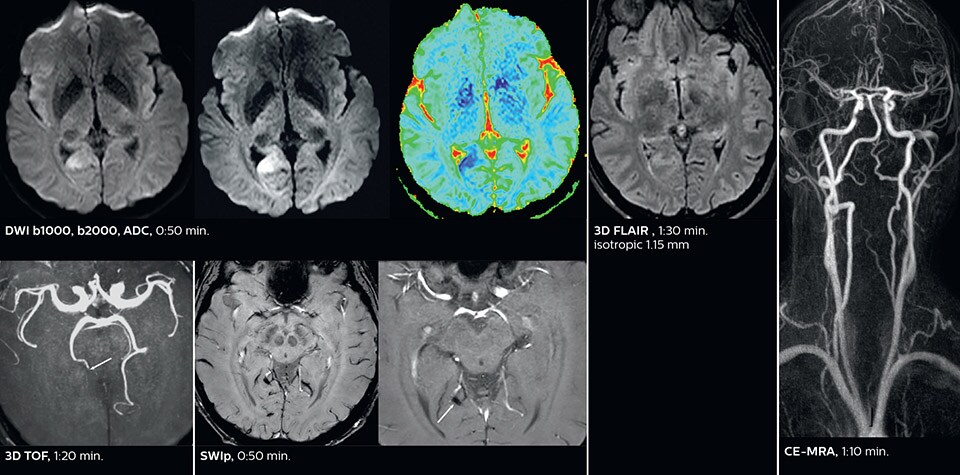

Dr. Savatovsky appreciates the improvements and flexibility that Elition with Compressed SENSE and MultiBand SENSE provides, particularly for stroke patients. “For stroke, it allows us to cut about 5 minutes off of our stroke protocol, or to keep the same acquisition time and get more insights.”   The ability to perform more sequences can help in making a swift and confident diagnosis. “For example, our stroke cases usually include the regular sequences that every center does (b1000 diffusion, FLAIR, time-of-flight angiography), but we also image supra aortic vessels, and we can replace a gradient echo sequence with a fast 50-second susceptibility-weighted sequence, and all of this doesn’t add much time. because all the regular sequences are accelerated on Elition.”   “The time savings with Compressed SENSE and MultiBand SENSE make it easier to add sequences to give us additional insights. Depending on the context and the first results, we might add a DSC perfusion to assess the ischemic penumbra, an ASL perfusion to help find an alternative cause in case of normal diffusion, or add a high-resolution T1 sequence for a stroke patient, to quickly assess wall imaging in emergency cases. The additional sequences can help improve patient management, because we can already consider some alternative diagnoses if the morphological MRI is normal.”

Using MultiBand SENSE allowed the staff to improve their diffusion quality. “Our diffusion sequence was already fast before, about 40 seconds. Now with Elition, it still lasts 40 seconds, but we improved the spatial resolution by 0.2 mm and use high b-values to be more sensitive to visualize changes related to acute stroke,” says Dr. Savatovsky.   “We now also developed a high resolution DTI sequence (1.3 x 1.3 x 2 mm) that can be reformatted and takes 2 to 5 minutes depending on the coverage. We use it every time we have a doubt, or when we expect the diffusion to be abnormal but don’t see that on the fast sequence. We occasionally spot small ischemic infarctions that would not have been visible with the regular diffusion sequence.”

This is an example of acute ischemic stroke with distal occlusion of the right posterior cerebral artery. Note the improved visibility of the ischemic territory on the diffusion weighted image with high b-value. The 3D FLAIR shows a distal PCA occlusion. The fast SWIp depicts the thrombus on the isolated second echo image. The total scan time (including SmartBrain, preparations and a fast 3D T1w TSE Gd) is 8:00 minutes.

In this patient with acute right motor deficit and aphasia, the b2000 diffusion weighted image is normal. The SWIp image demonstrates more prominent veins in the right hemisphere, which could reflect increased deoxyhemoglobin contents. Fast ASL shows low CBF regions in the left frontal lobe. A follow-up ASL after one hour demonstrates high CBF values in the same area. The final diagnosis was migraine with aura.